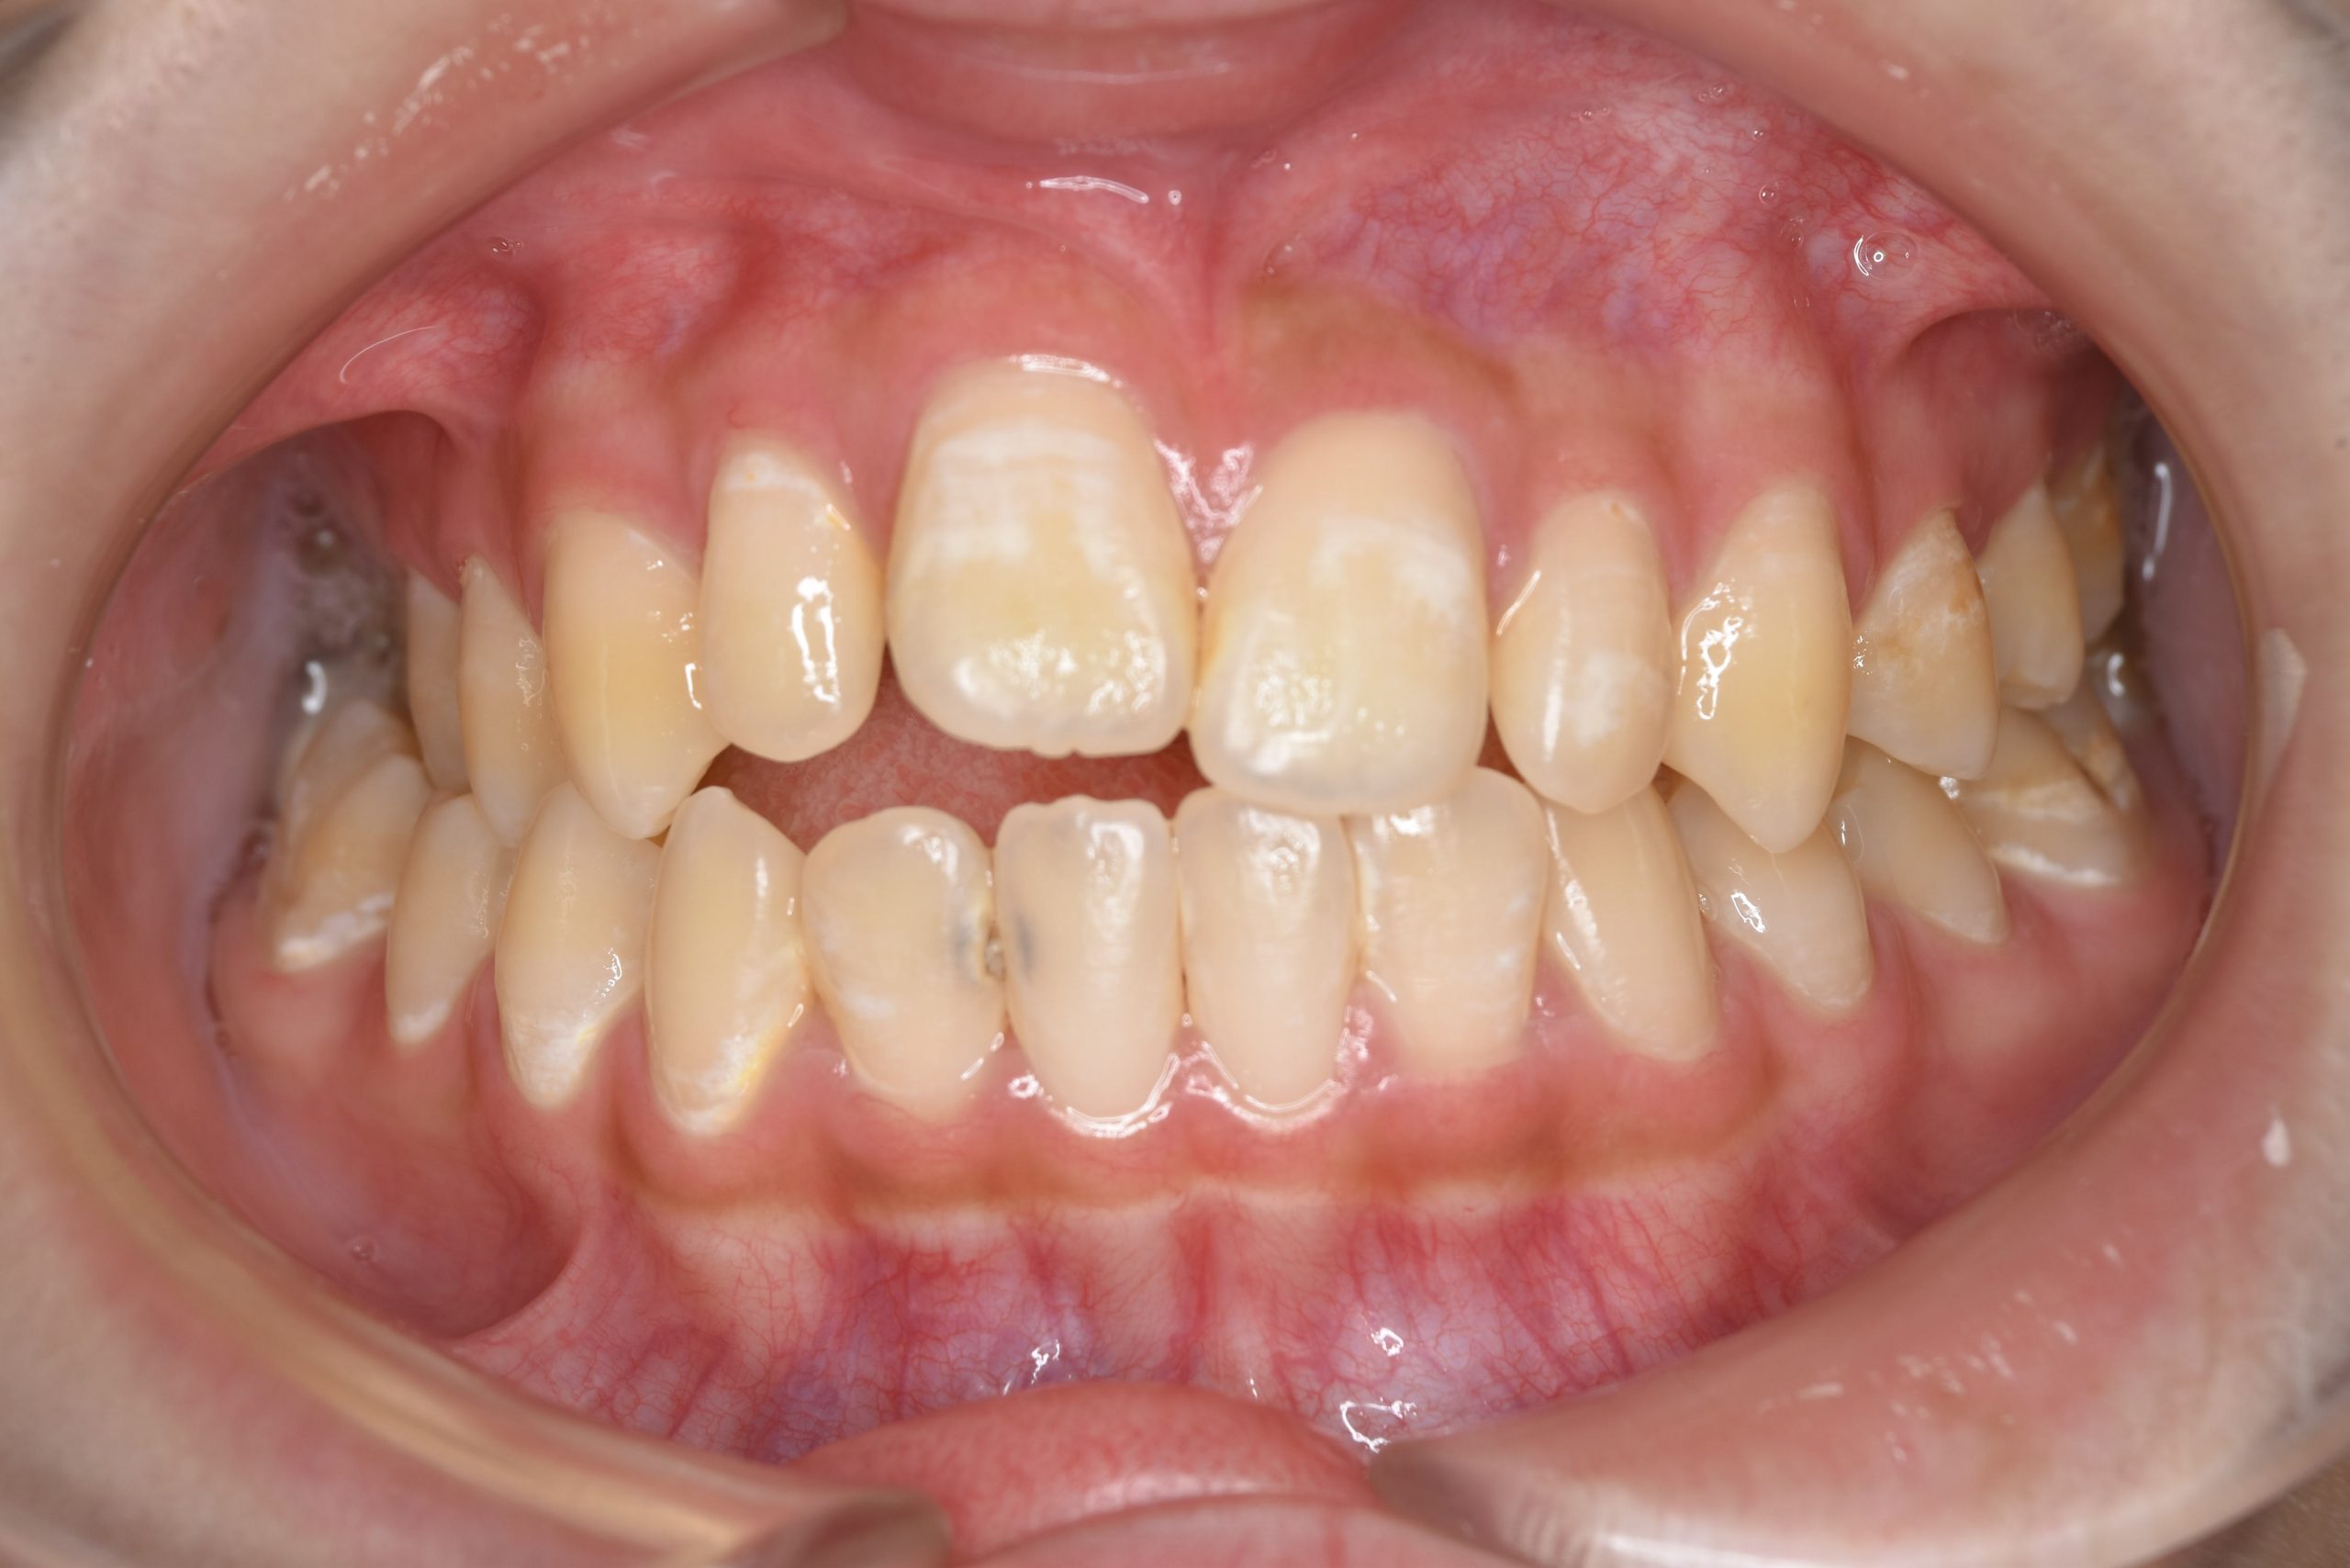

ビフォー

ワイヤー矯正治療|症例_032

主訴 歯並び|かみ合わせ

施術内容 MSEと下顎リンガルアーチを用いて上下顎骨を拡大した。

その後マルチブラケット装置を用いて非抜歯で歯牙を配列し良好な咬合を獲得した。

吸指癖と鼻閉症状は改善した。